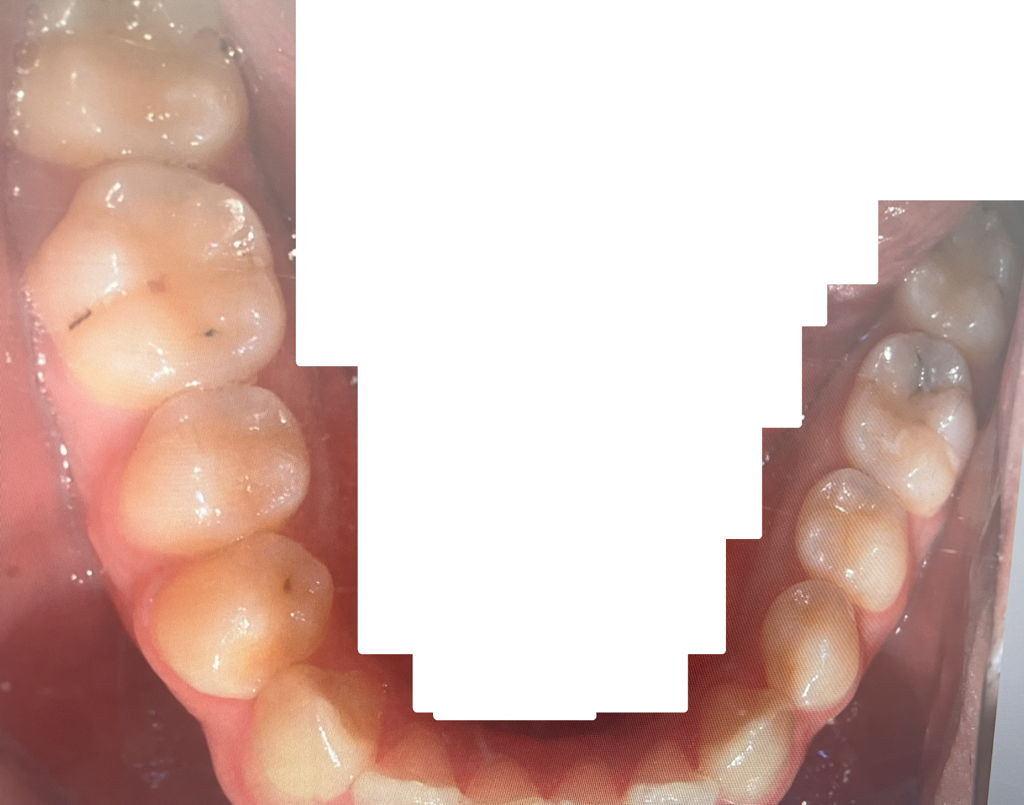

엑스레이 및 구강사진으로 충치진단

어떤 치아를 어떤 치료해야할지 알려주세요

그리고 인접면은 거의 정지우식 불가능하고

• 4번 째 사진

치아 사이에 즉, 인접면 충치가 다수 있으신거 같습니다. 저정도면 진행되는 충치이니 치료를 하시는게 좋을것같습니다.